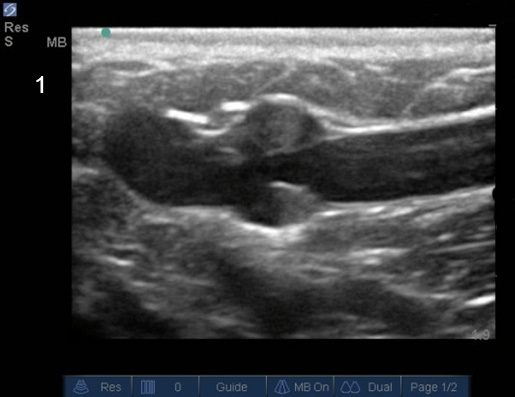

Noise Artifact in Vein Image